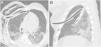

Con respecto a los dispositivos, fueron retirados en dos pacientes antes de realizar la TCP. Aun así, identificamos mal posición de algún dispositivo en 80% de los casos restantes siendo la más frecuente la incorrecta posición del tubo orotraqueal en relación con la carina. El caso más grave fue la incorrecta colocación de dos tubos torácicos en el mismo sujeto, como se muestra en la figura 2.